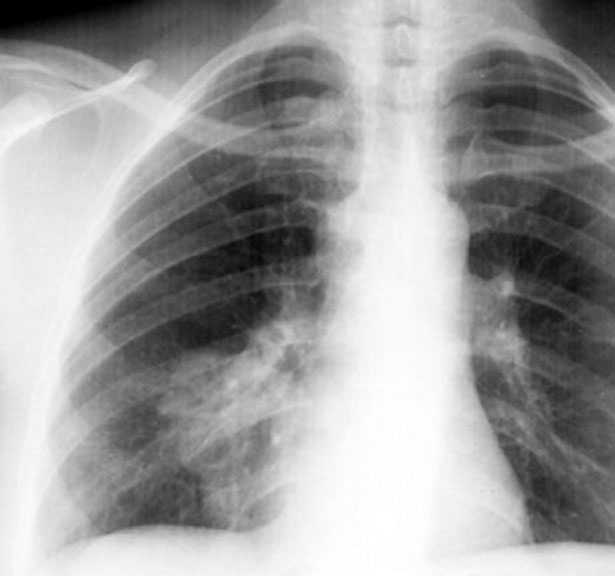

Wegener's Granulomatosis

• RML mass

• Paratracheal node

RML lesion